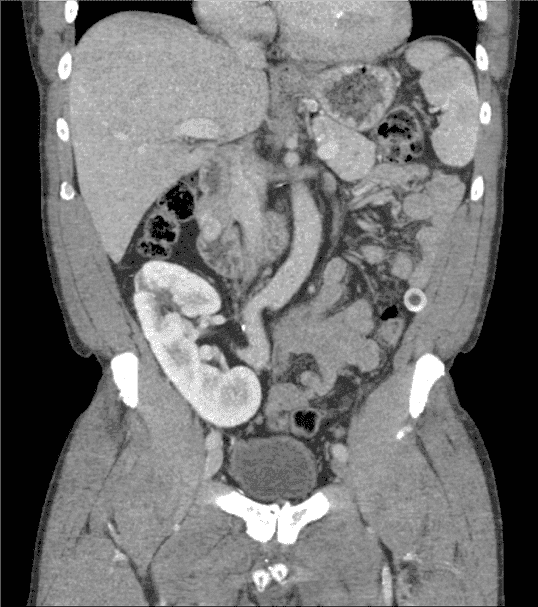

A proper workup of GIST requires imaging. GIST is best evaluated by cross-sectional imaging such as computed tomography (CT). They appear on CT scans as solid masses with smooth contours that are easily identified by IV contrast (Figure 1). Larger masses can show evidence of hemorrhage, necrosis, and degenerative areas on CT imaging, creating cavities or cysts that may contain air, air and fluid, or contrast medium. CT imaging can also assess for adjacent organ invasion and metastases [11].

Figure 1. Computed Tomography Scan of the Abdomen and Pelvis with IV Contrast.